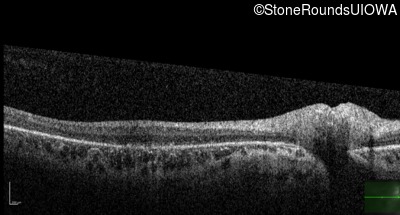

Optical Coherence Tomography - Left - 20/50 -1

Exemplar / OCT Stack